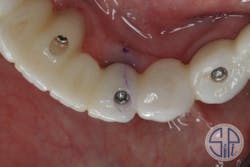

The fractured zirconia restoration was sectioned into two pieces, sandblasted, and then reseated as separate pieces. A new impression coping was placed on transmucosal abutment No. 27 (figure 7). All three pieces were luted together with resin as a new abutment level "pickup" impression (figure 8).

Figure 7: New impression coping placed on transucosal abutment No. 27

Figure 8: New abutment level "pickup" impression, with all three pieces luted together